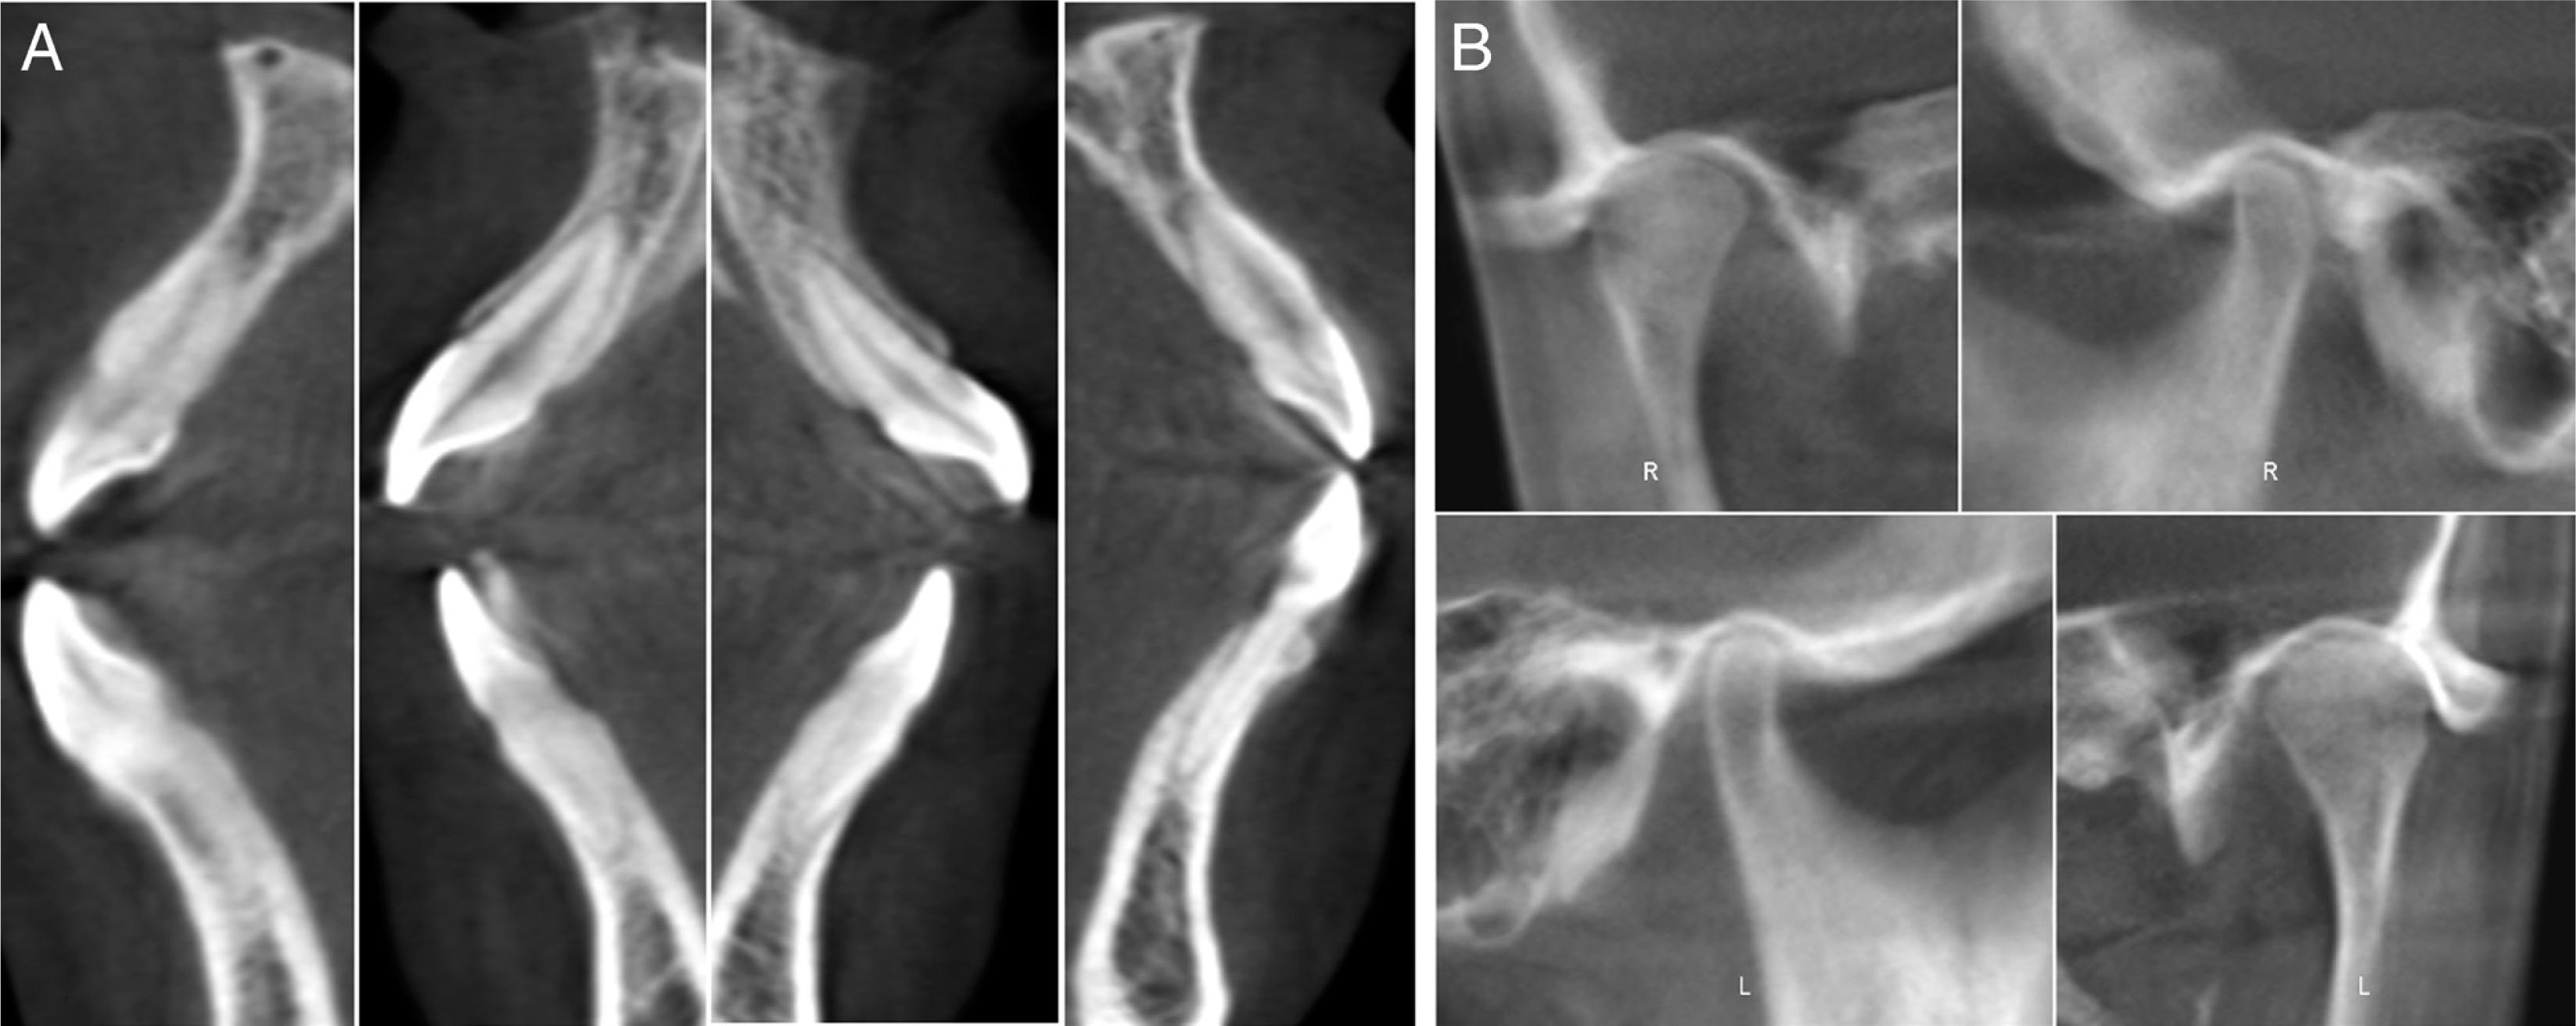

A 24-year-old female patient presented with a history of tongue thrust and mouth breathing but without a history of maxillofacial trauma or a non-nutritive sucking habit. The diagnostic records revealed that, based on the E line, the patient had a convex profile with a long face, a decreased nasolabial angle, a protrusive lower lip, and a shallow mentolabial sulcus. Further, the patient had incompetent and protruded lips at rest and in contact but with mentalis strain upon forcible closure. There was also a low smile line, and the smile arc was not consonant with the curvature of the lower lip (Figure 1). An intraoral examination showed an anterior open bite with no occlusal contact from the right first premolar to the left first premolar, a bilateral Class III molar relationship, and a Class III canine relationship on the right side but a Class I relationship on the left side. An analysis of the initial study models revealed that there was an anterior dental open bite of 6 mm, a decreased overjet (the overjet and overbite were measured on digital dental models using 3-shape software), a 3 mm curve of Spee, a mandibular midline deviation (1.5 mm to the left), and arch-length discrepancies of 5 mm in the maxilla and 3 mm in the mandible. The anterior and overall Bolton ratios were compatible. The maxillary dental arch was narrow, and the upper and lower arches were unmatched. A crossbite from the upper left canine to the second premolar was also noted during the examination. The maxillary right second molar was in scissor-bite with the mandibular right second molar (Figure 2). A cephalometric analysis revealed a skeletal open bite (SN/GO-GN 48°), an increased mandibular plane angle, a counter-clockwise rotation of the ANS-PNS plane (S-N/ANS-PNS 6°), proclination of the upper incisors (UI/ANS-PNS 129°), an interincisal angle of 108°, excessive lower anterior facial height and a short upper anterior facial height (Table I). A computed tomography scan of the anterior teeth revealed adequate labial and lingual bone volumes (Figure 3A). In addition, the initial panoramic radiograph and the radiographic and clinical examinations of the temporomandibular joints revealed no obvious abnormalities (Figure 4 and 3B). The patient was diagnosed with a Class III malocclusion (S-N/ANS-PNS 6°) and skeletal open bite (SN/GO-GN 48°) with an increased mandibular plane angle, a long face, a convex profile, and lip incompetence with mentalis strain. There was also proclination of the upper incisors, a crossbite, scissor-bite, mild crowding and midline deviation.

The pre-treatment labial and lingual bone volume of anterior teeth (A) and temporomandibular joint radiograph (B).